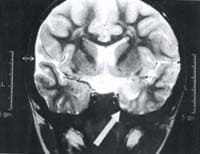

Se realizó junta médico-quirúrgica y para esta cita asistió la madre por primera vez. En la junta se analizó el cuadro y solo se aconsejó tomar una TAC como complemento al estudio. Aprovechando la presencia de la madre, se reinterrogó sobre el dolor en la pierna, que en los últimas semanas se había acentuado, y al referir disestesias y parestesias, no relatadas antes a pesar de interrogatorio dirijido, se remitió a Neurología. Allí al revisar de nuevo el EEG, se encontró actividad de punta onda centro-temporal derecha sugestiva de un foco a nivel mesial (figura No. 1). Suponiendo que se trataba de una lesión estructural y/o secuelar, que explicaba la sintomatología neurovegetativa, se ordenó Resonancia Magnética cerebral que confirmó la impresión inicial y se consolidó el diagnóstico de Epilepsia Neurovegetativa, precisando el tipo de lesión como Esclerosis Mesial Temporal (figura No. 2).

| Figura No.1 Caso clínico Dolor Abdominal Recurrente. En rostro trazado típico de onda punta temporal derecha en el E.E.G. que indica foco a nivel mesial. | Figura No. 2 Caso clínico. La flecha señala la zona del hipocampo con disminución global del lóbulo temporal derecho y disminución del volumen de los hipocampo correspondiente, típico de la esclerosis mesial. |